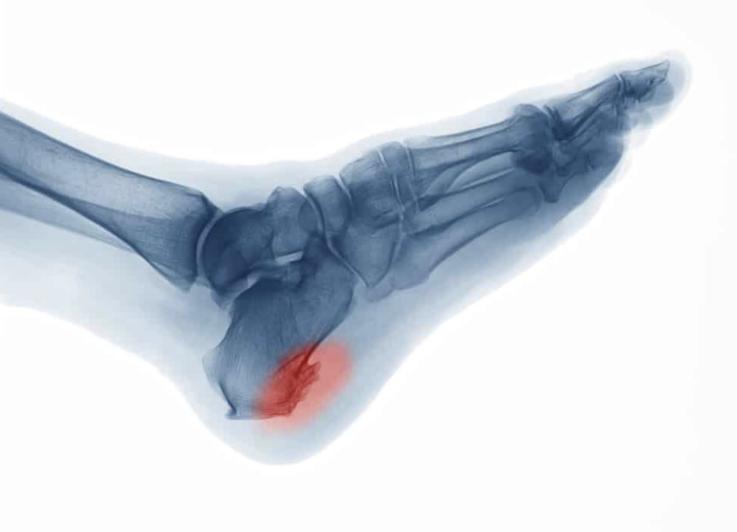

脚后跟长骨刺,主要是因为足底筋膜经常反复过度拉伸,足底筋膜就会出现退化、发炎的症状。反复的炎症会刺激患处的骨质,就会长出骨刺。 想要诊断骨刺,需要做X线检查,可以直接观察到骨刺的生增长情况。

临床上,一般的骨折可以通过X线检查来诊断,但轻至中度的应力性骨折早期可能不一定能从X线片中看得出来。 如果高度怀疑是应力性骨折,但X光又看不出时,就要做磁共振成像检查,可以有效发现骨膜和骨髓水肿范围。

癌症骨转移引起的脚后跟疼跟普通脚后跟疼的 区别 就是 ,疼痛会持续较长时间,而且休息和服用药物都无法缓解疼痛。 癌症骨转移的诊断主要是通过影像学检查,包括X线、骨扫描、CT、磁共振成像和PET扫描。必要时,还需要进行骨穿刺活检,可以明确骨转移的癌症类型。